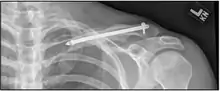

الأشعة السينية من كسر مفتت أعلاه تعامل مع جهاز تثبيت داخل النقي الدواء يمكن وصفه لتخفيف الألم، وكذلك تسديدة المضادات الحيوية أو الكزاز للأي فواصل الجلد. في الحالات الشديدة، قد تكون هناك حاجة لعملية جراحية من أجل وضع العظام في المواقف العادية باستخدام دبابيس، لوحات، ومسامير لعقد العظام معا.

والانقطاع في شكل العظام غالبا ما ينتج عن وجود كسر الترقوة وظاهرة للعيان من خلال الجلد، وإذا لم يعالج بالجراحة. وإجراء العمليات الجراحية وكثيرا ما يطلق على ORIF (مفتوح لحد الداخلية [لوحة] تثبيت) حيث يتم تثبيتها على التيتانيوم على شكل تشريحيا أو مسطحات الصلب على طول الجانب متفوقة من العظام عبر عدة مسامير. في بعض الحالات قد تتم إزالة اللوحة بعد الشفاء، ولكن هذا نادرا ما يطلب (على أساس التفاعل العصبية أو تفاقم الأنسجة)، وتعتبر عادة إجراء انتخابي. بدلا من ذلك، أجهزة تثبيت داخل النقي (داخل القناة النخاعية) يمكن زرعها لدعم كسر أثناء الشفاء. يتم زرع هذه الأجهزة داخل القناة الترقوة لدعم العظام من الداخل. المضاعفات الجراحية النموذجية هي العدوى، وأعراض عصبية القاصي شق (في بعض الأحيان إلى أقصى)، وغير النقابية.